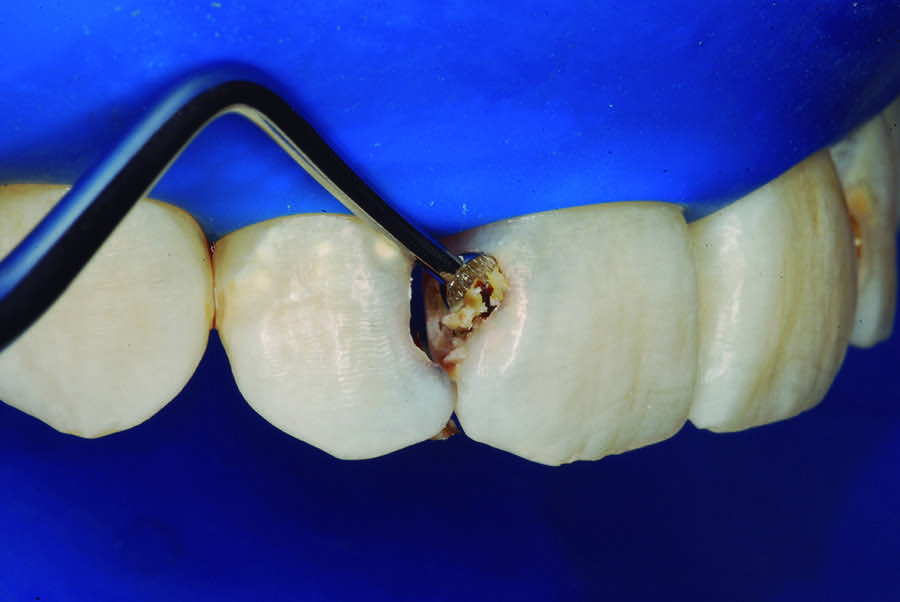

The partial pulpotomy was performed for tooth No. 7 due to the pulp exposure during the caries removal procedures (Figure 5). The superficial contaminated pulp tissue was removed with a No. 1012 spherical diamond bur at high speed with water cooling to allow a better reparative response. This procedure was limited to removal of the infected dentin and damaged pulp tissue, removing the injured odontoblast cell layer. During this step, the remaining pulp tissue was analyzed and found to have good consistency and abundant red bleeding (Figure 6). After the pulpotomy, a solution of calcium hydroxide was used for irrigation along with a sterile cotton pellet to achieve hemostasis and disinfection. After hemostasis, the tooth was treated with direct pulp capping: the exposed area was covered with calcium hydroxide powder (Figure 7) and calcium hydroxide cement (Figure 8). The cavity was provisionally restored with the use of a restorative GIC (Figure 9).

Fig 4. Manual excavator removing tooth decay.

Figure 4

Fig 5. Partial pulpotomy with No. 1012 diamond bur under water cooling.

Figure 5